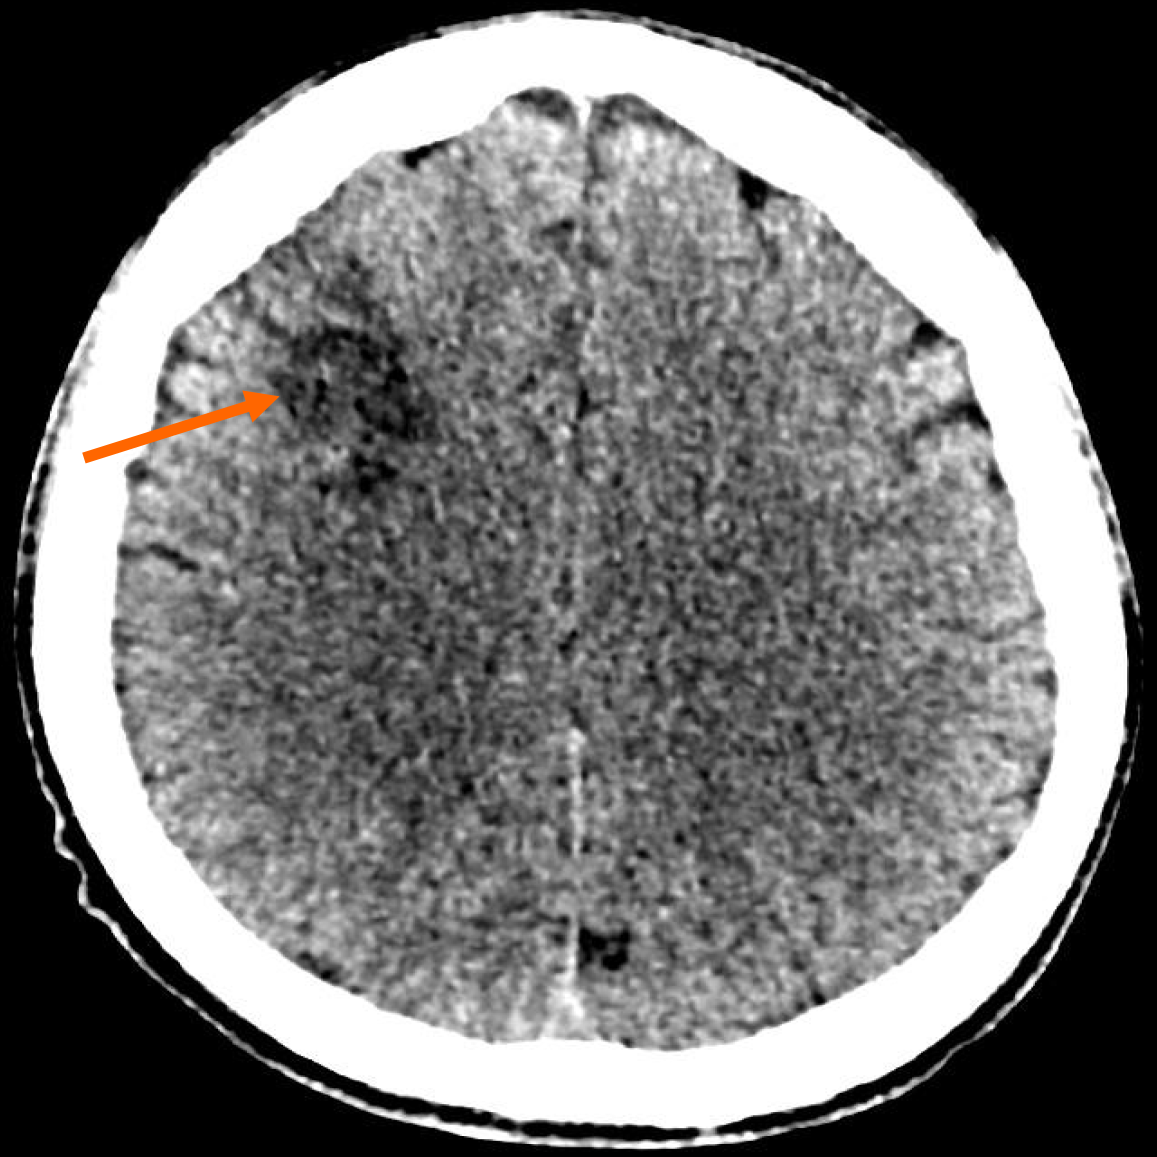

Figure 4

Non-enhanced computed tomography brain (axial view) with well-defined hypodensity at right fronto-parietal lobe, suggestive of a chronic watershed region infarct (orange arrow).